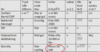

Förklara bilden

Förklara bilderna

VIKTIGT!

- Normalt bra svar

- Stimulering av nerv medianusnerven vid handled till m. abductus policis breves varpå svar ses med lite latens

- Stimulering av medianusnerven vid armbågsveck till samma muskel ses svar naturligt med längre latens

- Hastighet (CV) – 59 m/s

- Distal latens (DL) – 3 ms

- Axonal skada

- Låga amplituder

- Ledningshastighet relativt normal

- Demyeliniserad

- Låg hastighet

- CV – 12 m/s